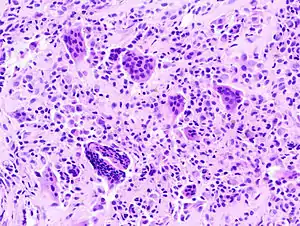

Micrograph of diffuse TGCT, also known as pigmented villonodular synovitis. H&E stain.

Per Nature, malignant Tenosynovial giant cell tumor tend to be "large, fleshy, and poorly circumscribed with areas of hemorrhage and necrosis" , while small histiocytes, larger mononuclear cells, siderophages were the given, histiologically.[11]